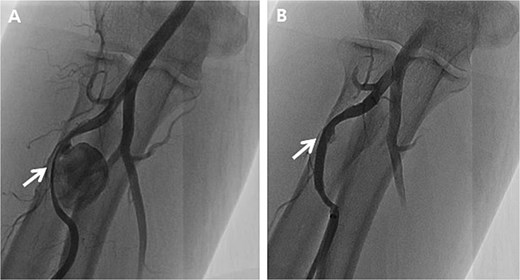

A 66-year-old male with a 1-month prior history of transradial coronary intervention visited hospital for aggravating pain and swelling on the right forearm. Upon physical exam, multiple masses were palpated at the arterial catheterization site as well as another unrelated site at the proximal forearm. An upper extremity CT scan was conducted to evaluate two different RAPs, one at the distal radial artery (arterial catheterization site) measuring 0.8 cm without a neck of pseudoaneurysm (Fig. 1A) and one at the proximal radial artery (Not related to arterial catheterization site) measuring 2.0 cm with a neck of pseudoaneurysm (Fig. 1B). Blood tests for vasculitis or autoimmune disease are not specific to confirm the possible causes of RAPs.

Preprocedural computed tomography of the right upper extremity. (A) Pseudoaneurysm at the distal radial artery which was arterial catheterization site (arrow); (B) Pseudoaneurysm at the proximal radial artery which was not related to arterial catheterization site (arrow).